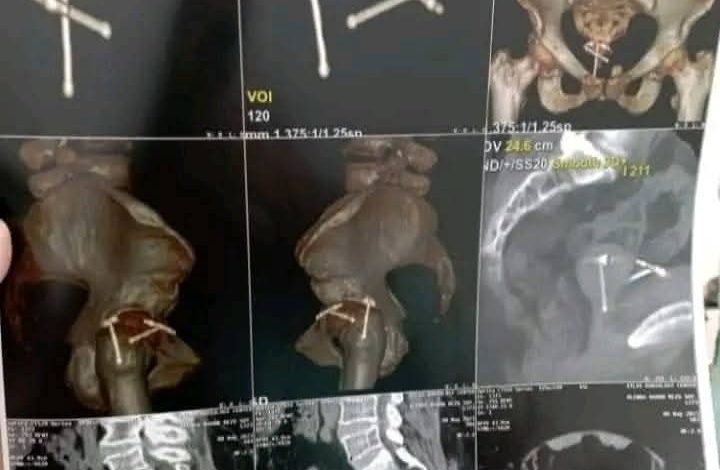

●قيمنا المريضه و وضعنا قدامنا كل الأسباب المحتمله للنزيف البولي في السيدات و علي رأسهم طبعا فين مكان اللولب التاني ؟ عملنا اشعة مقطعية للمريضة ودى تانى درس مهم للاطباء الشباب خد تاريخ مرضى بدقة كل كلمه مهمه و متستبعدتش أي كلمه تتقال و أي تشخيص محتمل واطلب فحوصات متاخدش الامر بسطحية ..

●لقينا اية.

– اللولب الاول نصة في الرحم ومخترق جدار المثانة ومكون علية حصوات اللولب التانى داخل الرحم…وفي بعض الحصوات في قناة مجرى البول …